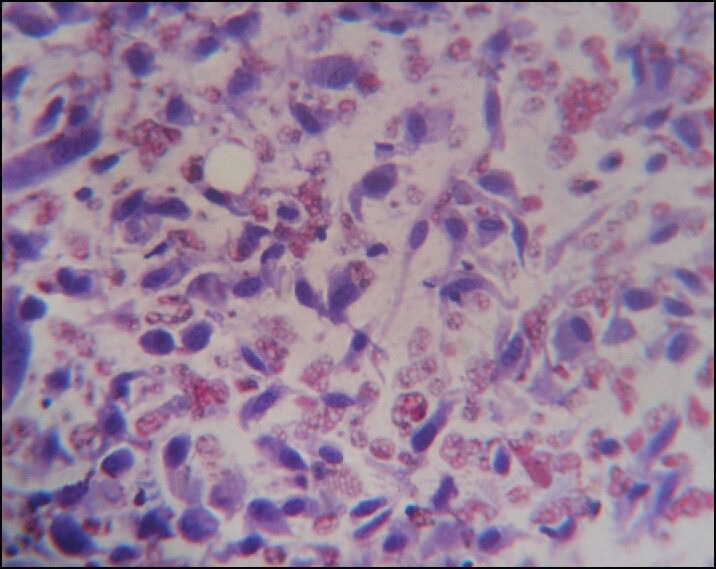

Among the diagnostic smears, three cases were benign lesions and rests were malignant (five cases). Benign lesions included two cases of infectious conditions in the form of adrenal tuberculosis and adrenal histoplasmosis [Figure 7]. We came across only one case of myelolipoma, which showed mature fat containing normal hematopoietic cells on cytological examination.

| Figure 7:Cytology of Histoplasma ×1000